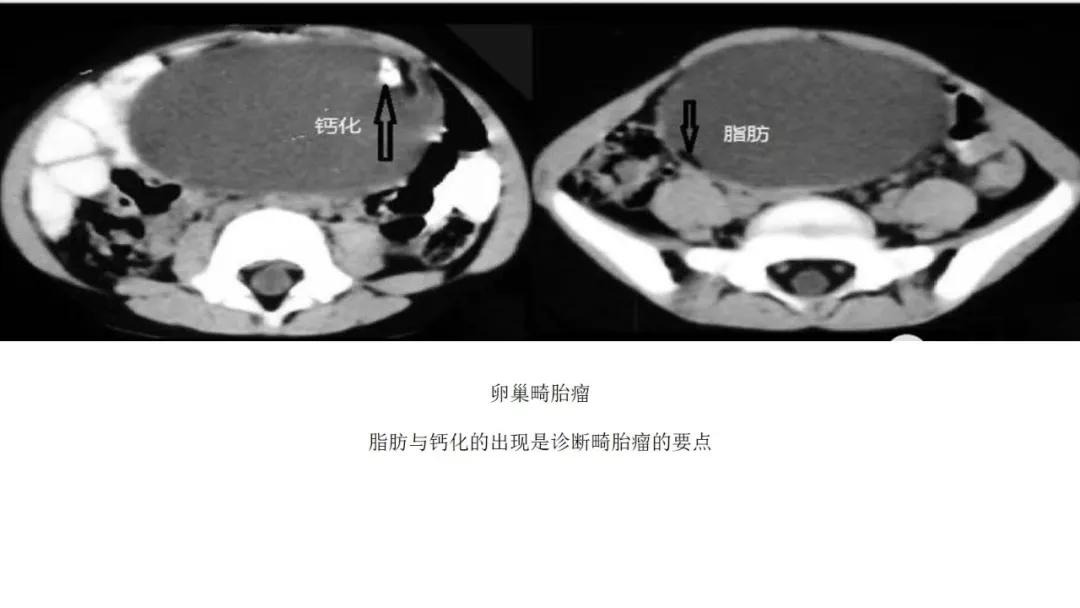

生殖细胞肿瘤占卵巢肿瘤的20%,以成熟畸胎瘤-皮样囊肿多见,良性多,恶性少。表现为囊实性混合性或实性肿块,大多数含有脂肪、钙化等特征。

良性者常呈囊性肿块,脂囊,脂液囊,液囊。少数混合成分,实性。壁光整可稍厚,囊内有脂、液分层现象,多数伴有粗大钙化或骨骼。

出现脂肪:畸胎瘤,囊性为主是成熟、实性为主是不成熟

出现钙化:浆液性肿瘤、卵泡膜纤维瘤、畸胎瘤、Brenner瘤